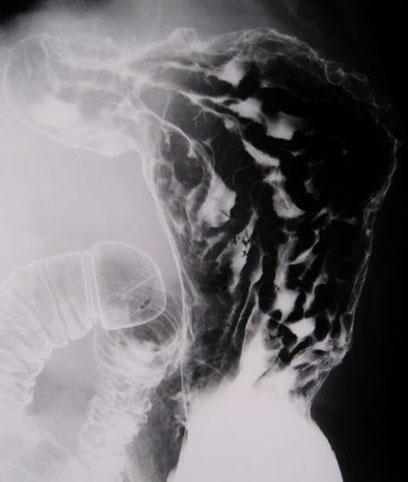

疾病(病理主体)的分类转移性肿瘤/

部位(按器官分)胃(部位)/2个以上

检查方法X线

肿瘤的肉眼分类4型(弥漫浸润型)/

肿瘤最大直径40以上